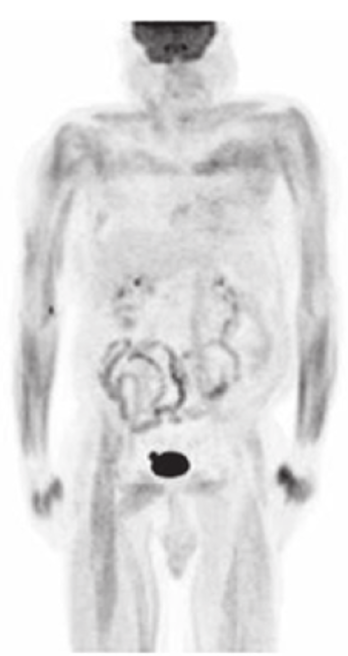

This FDG PET scan demonstrates:

Muscle uptake due to exercise